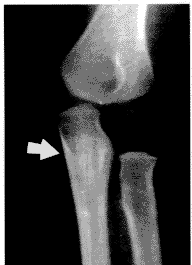

特异性骨骼改变 包括2种改变。一种是骨干条纹状改变,12例,于8个月~9岁之间均见此改变,其中>1岁者8例。X线片示高密度细条索影与骨干相平行,位于骨松质骨内,可延续延伸至干骺端(图1,2)。此12例中10例均伴有轻、中度脱钙。骨干条纹状改变均见于尺桡骨和股骨的长管状骨;二是干骺端两侧缘鸟嘴状突起,21例,见于股骨下端和胫骨上端大干骺端(图3)。本文37例患儿的各个年龄段都可以出现此种改变。

图1 苯丙酮尿症男孩, 5岁,示桡骨干远端松质骨内细

条状高密度影,与骨干相平行。骨年齿测量相当 2 岁左右